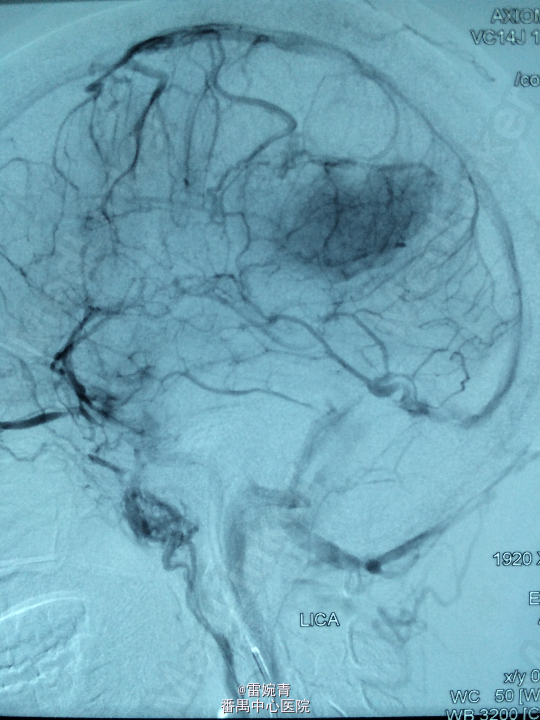

诊断:脑膜瘤 处理:先行DSA检查以明确脑膜瘤的供血动脉情况,见:肿瘤染色,肿瘤主要由左侧眼动脉供血,用Glubran胶将其闭塞,后择期行手术切除治疗。术后病理证实为脑膜瘤。